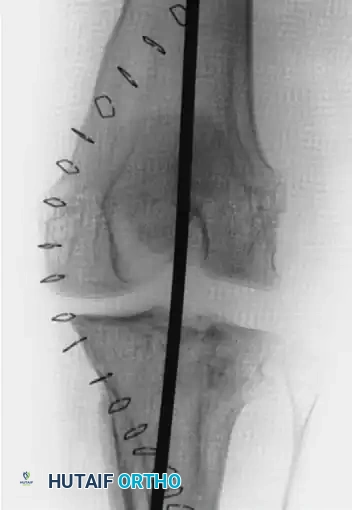

Given the 6-week duration, an open reduction was mandated. Extensive soft-tissue releases were performed to mobilize the contracted structures. Following successful reduction of both the tibiofemoral and patellofemoral joints, the inherent instability required temporary internal fixation. A smooth Steinmann pin was passed longitudinally through the quadriceps mechanism, traversing the femur and anchoring into the tibia to maintain alignment.

Figures C and D: Anteroposterior and lateral radiographs at the time of open reduction and internal fixation with a smooth Steinmann pin through the quadriceps mechanism of the femur and tibia.